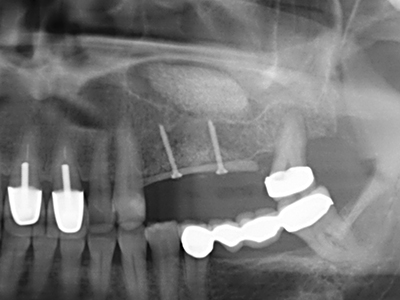

En la extracción de bloques óseos la piezocirugía también presenta ventajas adicionales: Además de la alta precisión en la osteotomía que ya se ha descrito antes, se ha comprobado que el uso de los delgados insertos de sierra resulta especialmente cuidadosas con el hueso. Frente a esto, sobre todo cuando se usan las fresas de Lindemann, cabe esperar pérdidas en la extracción significativamente más altas debido al mayor grosor de la parte frontal del cabezal (Lakshmiganthan, Gokulanathan et al. 2012). La separación basal que se necesita en particular en los injertos de bloque extraídos de forma retromolar se ve facilitada mediante sierras perpendiculares especialmente previstas a tal fin, lo que permite considerar que la cirugía piezoeléctrica es un procedimiento preciso y seguro para la obtención de bloques de hueso en el área retromolar (Happe 2007) (fig. 1-12).

Con el uso de sierras piezoeléctricas la división se efectúa de forma especialmente cuidadosa y sin pérdidas importantes de las dimensiones, por lo que no se han encontrado diferencias significativas entre los implantes realizados en el maxilar dividido y en la cresta alveolar no deficitaria (Chiapasco, Zaniboni et al. 2006, Danza, Guidi et al. 2009). No obstante, precisamente en la partición profunda y limitada de forma local, es preciso asegurarse de que exista una adecuada irrigación por agua para evitar que se produzcan sobrecargas térmicas en las áreas de osteotomía apical.